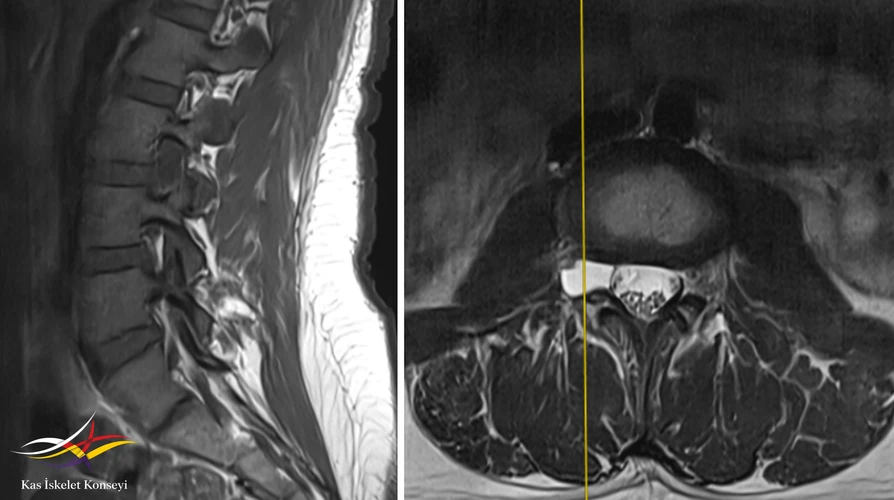

Resim 1. Lomber MRG. Solda T1 ağırlıklı sagittal, sağda T2 ağrılıklı aksiyal kesit: L3-4 sevitesinde sağda foramende kistik lezyon görülmekte (perinöral kist).

L3-4 seviyesinde sağ nöral foramen yerleşimli lezyon, tüm sekanslarda BOS intansitesine eş dansitede olmasına binaen bir perinöral kist olarak değerlendirildi. Bu lezyonun komşu kökü basarak semptomatik olabileceği, ancak bu yerleşimdeki bir kistin hastadaki gibi bel ve sol bacak ağrısından çok, sağ bacak ağrısı ve sağ L3 kök bulguları yapmasının bekleneceği düşünüldü. Bel ve sol bacak ağrısının L5-S1 seviyesindeki ılımlı disk dejenerasyonuna bağlı olabileceği öngörüldü. Sağ bacakta radiküler bir ağrı olmadıkça perinöral kiste yönelik radyolojik takibe gerek görülmedi.